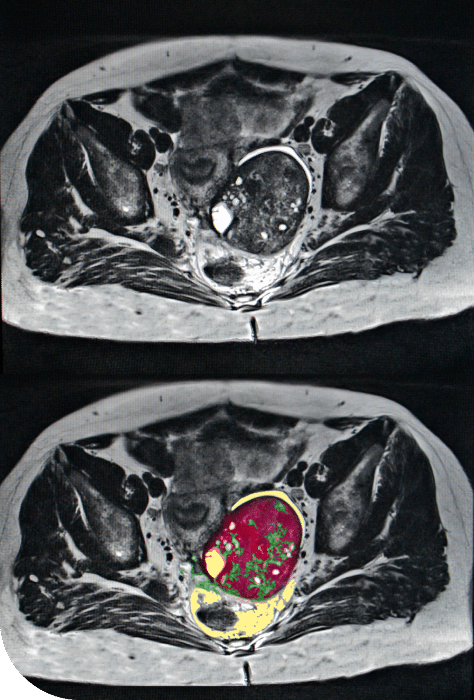

Peritoneal Mesothelioma Misdiagnosis

The symptoms of peritoneal mesothelioma are nonspecific and difficult to diagnose. The most common symptom is a distended abdomen, occurring in 30 to 80 percent of patients, according to the Annals of Translational Medicine. The second most common complaint is nonspecific abdominal pain, occurring in 27 to 58 percent of peritoneal mesothelioma patients.

Ovarian mesothelioma is very rare, and it is difficult to differentiate from ovarian cancer and peritoneal mesothelioma. Ovarian mesothelioma may spread to the peritoneum before mesothelioma is diagnosed. Additionally, ovarian cancer and mesothelioma have similar properties on radiological tests, and the cells of both types look similar when viewed under a microscope.

This similarity means ovarian mesothelioma may be misdiagnosed as peritoneal mesothelioma or ovarian cancer. Misdiagnosing ovarian mesothelioma can lead to underestimation of the tumor, resulting in less effective or less targeted treatment.

The diagnosis of ovarian mesothelioma should be confirmed via immunohistochemical staining. This is the most reliable means to distinguish ovarian mesothelioma cells from ovarian cancer cells.